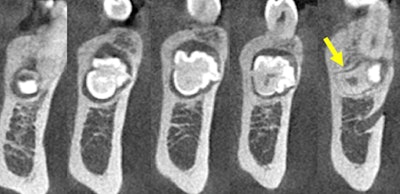

Figure 1: Reformatted CBCT panoramic film.

Figure 2: CBCT coronal projections (anterior to posterior).

A hyperdense lesion (radiopaque) surrounded by a hypodense ring with very well-defined

borders. A distal extension of the lesion takes the form of a primitive root. The lesion is in the middle of the mandible. Tooth #21 is slightly mesially displaced. Initial resorption is observed at the distal third aspect of the root of tooth #21. The lesion is displacing apically the mental foramen.